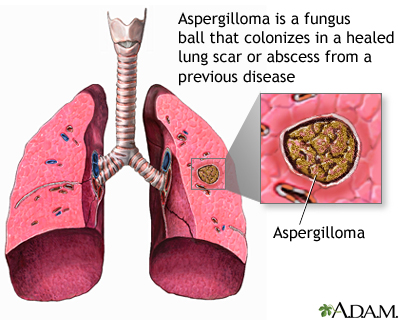

Pulmonary aspergilloma is a mass caused by an infection by the fungus aspergillus. It usually grows in preexisting lung cavities. The infection can also appear in the brain, kidney, or other organs.

Aspergillosis is an infection caused by the fungus aspergillus. Aspergillomas are formed when the fungus grows in a clump in a lung cavity. The cavity is often created by a previous condition. Cavities in the lung may be caused by diseases such as:

The most common species of fungus that causes disease in humans is Aspergillus fumigatus.

Aspergillus is a common fungus. It grows on dead leaves, stored grain, bird droppings, compost piles, and other decaying vegetation.